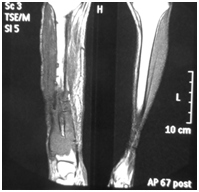

Figure 2 MRI coronal cut of the leg showing local recurrence in case 2